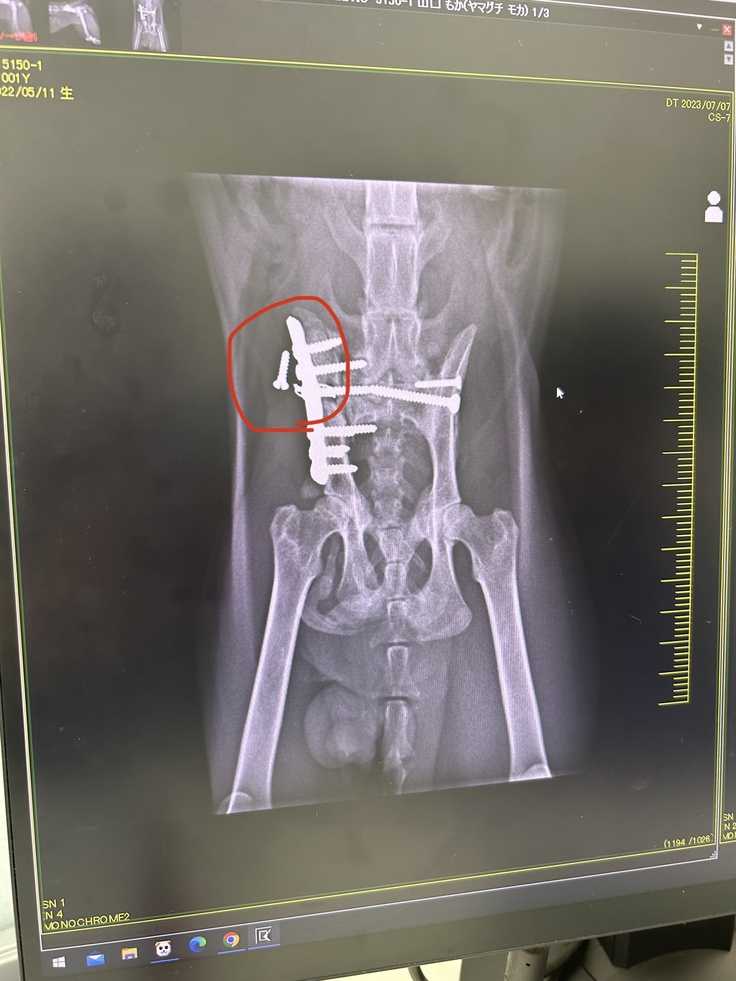

レントゲンを撮ると、前回取れかかっていた

ボルトは完全に取れていました。

↓今回のレントゲン写真

取れているボルトは特に影響がない為

様子を見ることになりました。

骨自体はもうしっかりくっついている為

生活の制限をせずに、普通に動いて

大丈夫と先生から許可がおりました✨